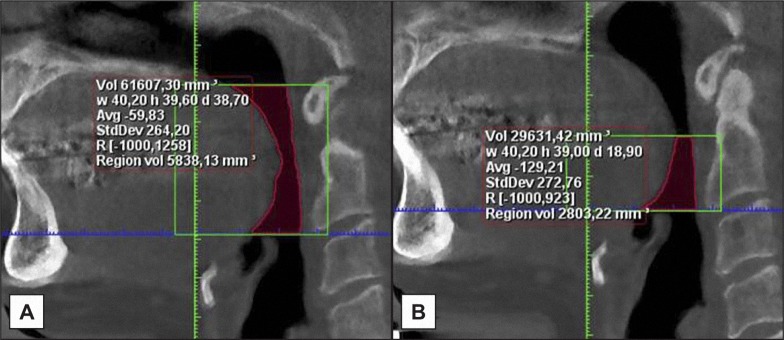

Material and methods: The sample comprised 53 obstructive sleep apnea (OSA) patients of which 32.1% had upper spine morphological deviations. Accordingly two groups were defined: 17 OSA patients with morphological deviations in the upper spine and 36 without upper spine deviations. Pharyngeal airway dimensions in terms of distances, cross-sectional areas and volume and upper spine morphological deviations were evaluated on cone-beam computed tomography. Head posture was evaluated on two-dimensional generated lateral cephalograms. Differences were analysed and adjusted for age and gender by multiple linear regression analysis.

Results: OSA patients with upper spine morphological deviations had a significantly more backward and curved neck posture (OPT/HOR, P < 0.01; OPT/CVT, P < 0.05) compared to OSA patients without spine deviations. No significant differences were found in airway dimensions between patients with and without upper spine deviations. In the total group significant associations were found between head posture and pharyngeal airway distances and cross-sectional area at the nasal floor, epiglottis and hyoid bone level (P < 0.05, P < 0.01, P < 0.001). No significant association was found between head posture and airway volume.